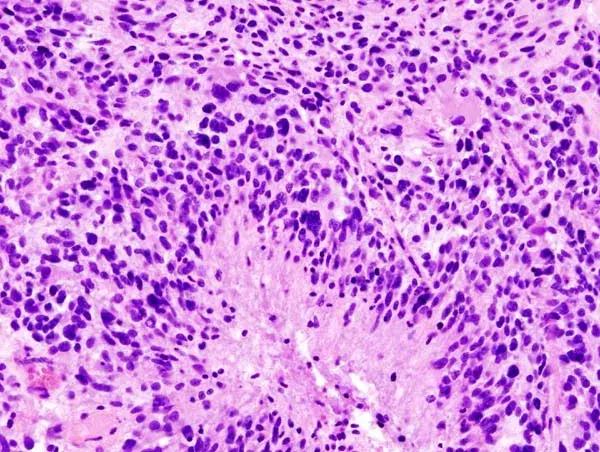

图 | 胶质母细胞瘤(来源:维基百科)

胶质母细胞瘤是最常见且具有侵袭性的成人脑肿瘤,占所有胶质瘤的 56% 和所有原发性脑肿瘤的 15%。

作为神经系统最常见的恶性肿瘤,脑胶质瘤恶性程度高、生长快、病程短、术后易复发且高致残,被认为是神经外科治疗中最棘手的难治性肿瘤之一。在脑胶质瘤中,胶质母细胞瘤的恶性程度最高,患者五年生存率低于 5%,尚不及肺癌五年生存率的 1/3,预后极差。